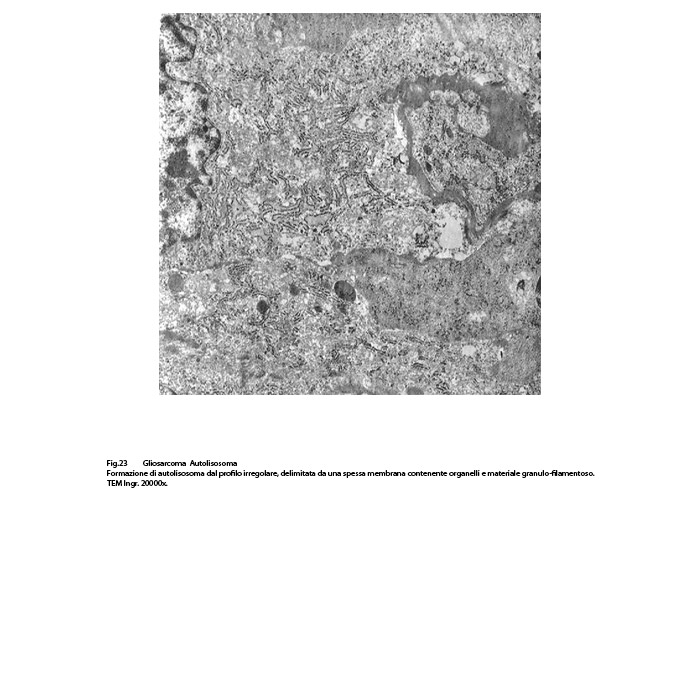

AUTOFAGOSOMI E AUTOLISOSOMI

L’autofagosoma è un focolaio vescicoloso endocellulare,di diverse dimensioni,di forma sferoidale,delimitato da una membrana a doppio strato;al suo interno si ritrovano materiali biologici eterogenei di aspetto granuloso,filamentoso,amorfo,tubulare e nei focolai voluminosi anche organelli citoplasmatici o frammenti nucleari.

Dopo questa fase di accumulo del cargo,segue quella della fusione tra l’autofagosoma e un lisosoma con formazione di una nuova struttura indicata con il termine di autolisosoma.

Tutto l’insieme così fuso viene sottoposto a un processo di degradazione da parte delle idrolasi lisosomiali e i prodotti così degradati,ridotti a entità di molecole semplici sono riversati nel citosol per essere riutilizzati nei processi di biosintesi o di attività energetiche. ( Antioxid Redox Signal 2014;20:460-473).

Gli autolisosomi inizialmente mostrano una doppia membrana di contorno,successivamente la membrana interna viene demolita dagli enzimi lisosomiali e appaiono come sub strutture vescicolose delimitate da una membrana a monostrato; pertanto si distinguono con difficoltà dai lisosomi secondari.(Margit Pavelka, Jurgen Roth: Functional Ultrastructure,Springer Verlag, 2015).

Tutto ciò è espressione biologica del processo di autofagia,quale meccanismo dinamico e attivo in numerose situazioni di fisiologia e patologia cellulare Essa si manifesta e si evolve in quanto è indotta da fattori nutrizionali,metabolici,ossidativi,infettivi,degenerativi, genotossici, proteolitici, neoplastici e in quelle situazioni da stress del reticolo endoplasmico e da disfunzione mitocondriale che mettono a rischio l’omeostasi cellulare.(Science,2011;334:358-362:)(Cell,2012;148:1145-115) (Nat.Rev.Cancer,2012;12:401-410).

Nel citoplasma delle cellule di gliosarcoma esaminate sono stati riscontrati con frequenza focolai di autofagosomi e di autolisosomi; i primi si riconoscono quali corpi ovoidali o rotondeggianti i quali sono demarcati da una membrana a doppio contorno e contengono nel loro spazio cavo materiale granuloso,filamentoso ed amorfo; i secondi,gli autolisosomi, sono delimitati da una membrana a monostrato,spesso notevolmente ispessita per sovrapposizione di materiale amorfo;il loro contenuto è rappresentato da materiale biologico in varie fasi di degradazione.

Fig.22  Fig.23

Fig.23  Fig.24